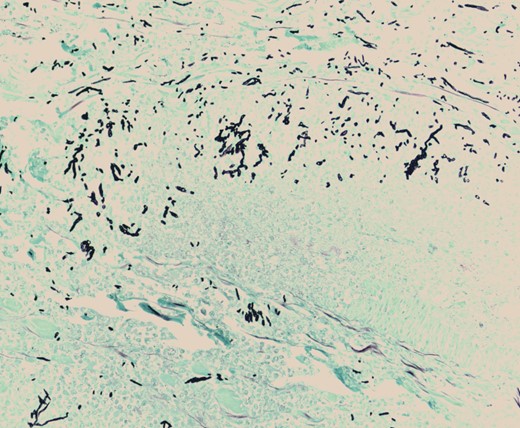

Pathologic evaluation of the resected bowel revealed hemorrhagic, gangrenous bowel (Fig. 1) and granular friable, ulcerated mucosa (Fig. 2). Microscopically, there were areas of transmural bowel necrosis (Fig. 3) and fungi within the bowel wall, artery wall and lumen (Fig. 4). Gomori Methenamine Silver stain was characteristic of Aspergillus species (Fig. 5).

Gomori Methenamine Silver stain highlighting fungal forms, some dichotomous, with frequent septation, characteristic of Aspergillus species.